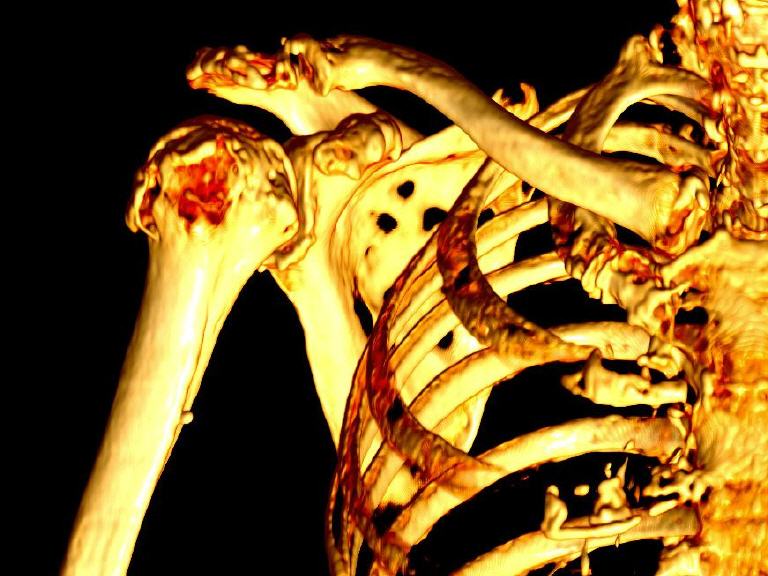

- CTs der Knochen zur Fraktursuche und OP-Vorbereitung